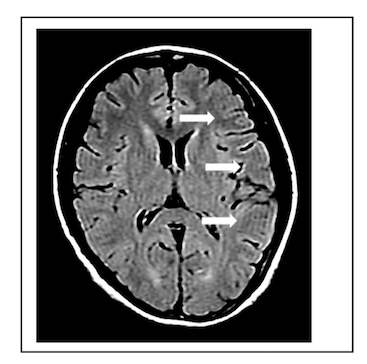

15-36 頭部の T2 強調画像を以下に示す。矢頭(▽)のアーチファクトに関する正しい記述はどれか。3つ選べ。

MRI認定 総集 ランダム